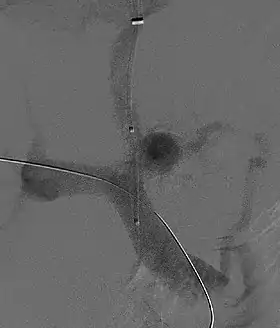

![]() Fluoroscopic image of TIPS in progress. A catheter has been passed into the hepatic vein and after needle puncture, a guidewire was passed into a portal vein branch. The tract was dilated with a balloon, and contrast injected. A self-expandable metallic stent has yet to be placed over the wire. | |

Transjugular intrahepatic portosystemic shunts are typically placed by an interventional radiologist under fluoroscopic guidance.[9] Access to the liver is gained, as the name 'transjugular' suggests, via the internal jugular vein in the neck. Once access to the jugular vein is confirmed, a guidewire and introducer sheath are typically placed to facilitate the shunt's placement. This enables the interventional radiologist to gain access to the patient's hepatic vein by traveling from the superior vena cava into the inferior vena cava and finally the hepatic vein. Once the catheter is in the hepatic vein, a wedge pressure is obtained to calculate the pressure gradient in the liver. Following this, carbon dioxide is injected to locate the portal vein. Then, a special needle known as a Colapinto is advanced through the liver parenchyma to connect the hepatic vein to the large portal vein, near the center of the liver. The channel for the shunt is next created by inflating an angioplasty balloon within the liver along the tract created by the needle. The shunt is completed by placing a special mesh tube known as a stent or endograft to maintain the tract between the higher-pressure portal vein and the lower-pressure hepatic vein. After the procedure, fluoroscopic images are made to show placement. Pressure in the portal vein and inferior vena cava are often measured.